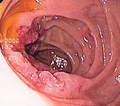

صورة ثابتة من منظار داخلي لقرح مريئية شوهدت بعد تحزيم banding دوالي المريء، في وقت الفحص بالمنظار المريئي المعدي الإثنا عشري | |